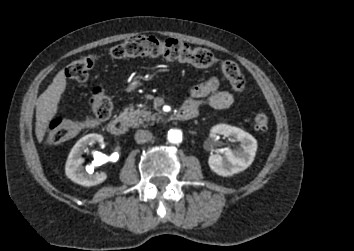

Мультиспиральная компьютерная томография почек и мочевыводящих путей  является высокоинформативным методом исследования, основанном на использовании воздействия рентгеновских лучей на органы и ткани человека. Методика предусматривает послойное сканирование области почек, мочевыводящих путей и получение снимков исследуемой области в мельчайших подробностях.

Для улучшения визуализации патологических очагов (различных кист или новообразований) в некоторых случаях дополнительно применяется контрастное усиление. Для этого пациенту внутривенно вводится йодсодержащее контрастное вещество, которое накапливается в патологически измененных участках и вызывает их яркое контрастирование на фоне здоровых тканей.

МСКТ почек и мочевыводящих путей с контрастированием позволяет выявить опухолевые образования на ранних стадиях, отличить доброкачественную опухоль от злокачественной, определить размеры опухоли, точную локализацию и степень распространения в окружающие ткани. Компьютерная томография почек с внутривенным болюсным контрастированием необходима для определения тактики лечения и объема оперативного вмешательства.

В клинике «Доступная медицина» исследование проводится с помощью современных мультиспиральных томографов экспертного уровня TOSHIBA AQUILION, которые производят сканирование области почек в виде тончайших срезов с шагом от 0,5 мм, затем обрабатывают полученные данные и выдают трехмерные изображения отсканированной зоны.